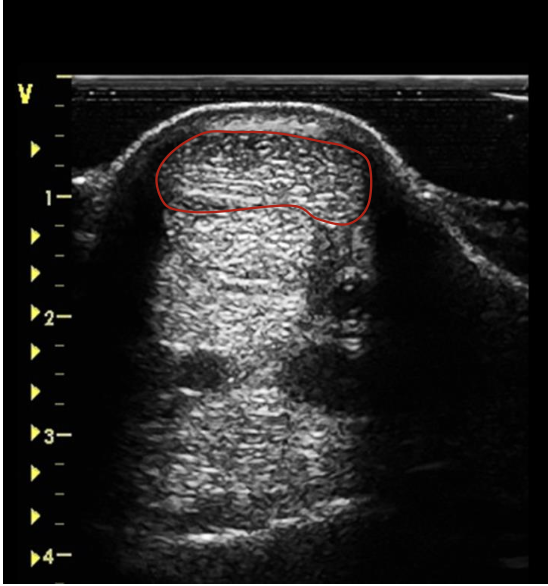

what is the red circling?

SDFT just below the carpal joint